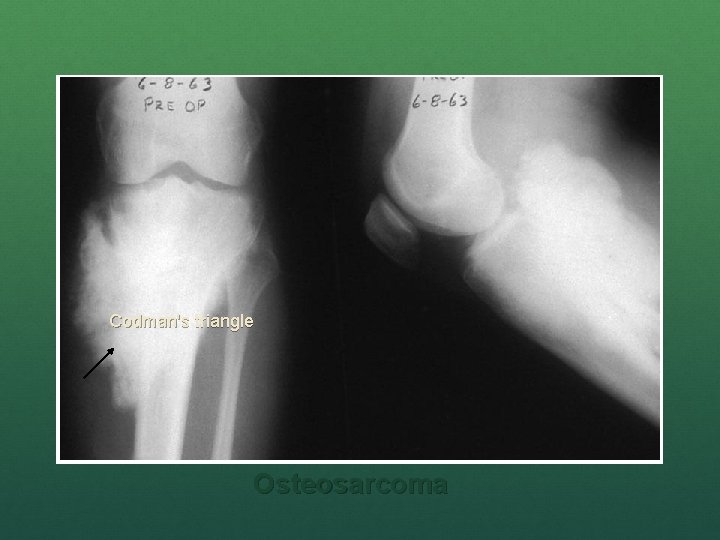

n Classic X-ray findings: 1. 2. 3. 4. Codman's triangle (periosteal elevation) Sunburst pattern/Sunrays appearance Bone destruction Ill-defined margins

Codman’s triangle Sunrays appearance Osteosarcoma

Codman's triangle Osteosarcoma